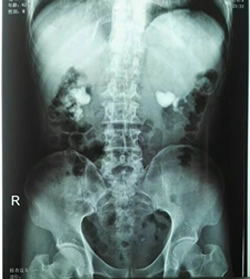

据悉,在帮扶期间,高锐同志积极带领泌尿外科医护人员开展新技术、新业务,开创了5项固原市“首例”手术:输尿管软镜下肾结石碎石取石术、经皮肾镜复杂性肾结石碎石取石术、腹腔镜下结核肾切除术、阴茎癌根治术+腹腔镜下双侧腹股沟淋巴结清扫术、输尿管狭窄高压球囊扩张术,使原州区人民医院泌尿外科诊疗技术水平跃居榜首,得到了同行们的肯定。

高锐副主任医师带领泌尿外科医护人员开展“首例经皮肾镜下复杂肾结石碎石取石术”